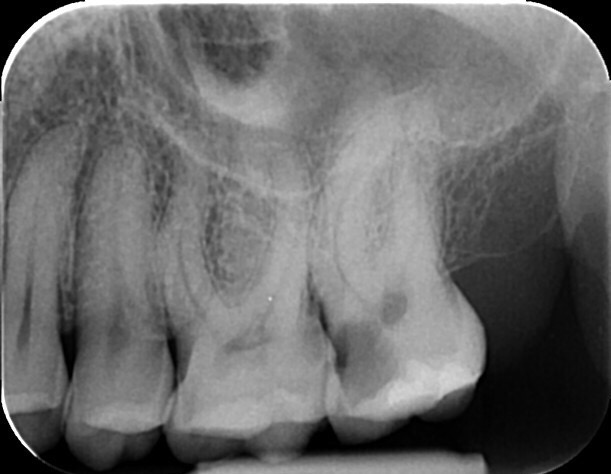

Zobe moramo zdraviti kadar pride do vnetja zobnega živca (pulpe) ali njegovega odmrtja (gangrena). Če kariesa ne odstranimo pravočasno, ta doseže zobni živec. To je lahko za vas popolnoma neboleče in brez težav, običajno pa se kaže s klasičnim zobobolom, ki se po moči lahko meri z najhujšimi telesnimi bolečinami. Zdravljenje zoba ponavadi zahteva več obiskov, ravno pri tem posegu pa je uporaba operativnega dentalnega mikroskopa najpomembnejša. Med zdravljenjem se poslužujemo tudi pomoči rentgenskih posnetkov, v zelo zahtevnih primerih pa tudi CBCT slikanja (cone-beam computed tomography – ali po slovensko – računalniška tomografija).

Granulom je kronično vnetje na koncu korenine zdravljenega ali gangrenoznega zoba. Vnetje povzročajo bakterije, ki so ostale v zobni korenini po zdravljenju. Skoraj 90% vseh granulomov ne povzroča bolečin. Zobozdravniki pa radi označujemo granulome z izrazom “tempirana bomba”. Granulom lahko namreč 10, 20 ali celo več let ne dela težav, počasi raste in topi kost, na enkrat pa izbruhne in vam začne delati ogromne težave. Glavne težave so bolečina, huda oteklina, vročina in splošno slabo počutje.Zato je nujno, da granulome opazimo pravočasno s pomočjo rentgenske diagnostike in jih skušamo s pomočjo endodontskega zdravljenja pozdraviti. Pogosto je ob izbruhu namreč edina rešitev odstranitev (puljenje) zoba.

Mnogo ljudi ima enega ali več zdravljenih zob. Zdravljenje zob je, zaradi komplicirane anatomije (zgradbe) zob, zelo zahtevno. Zato je žalostna resnica, da je večina zob, ki je bila zdravljena pred več kot 10 leti, zdravljena slabo. Take zobe je potrebno rentgensko kontrolirati, in v primeru, da opazimo na koncu korenin kronične spremembe, tudi ponovno zdraviti. Ponovno endodontsko zdravljenje lahko vključuje tudi poseg apikotomije. Če zdravljenje iz določenih razlogov ni možno, ni uspešno, ali pa je napoved izida zelo slaba, svetujemo odstranitev zoba in nadomeščanje z zobnim vsadkom ali mostičkom.